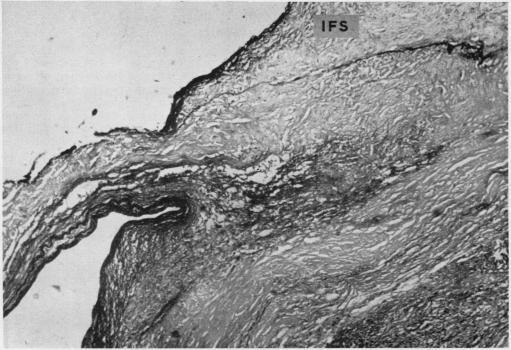

HOMOGRAFT AORTIC VALVE REPLACEMENT IN AORTIC INCOMPETENCE AND STENOSIS.

Thorax. 1964 Mar;19(2):131-50. doi: 10.1136/thx.19.2.131.